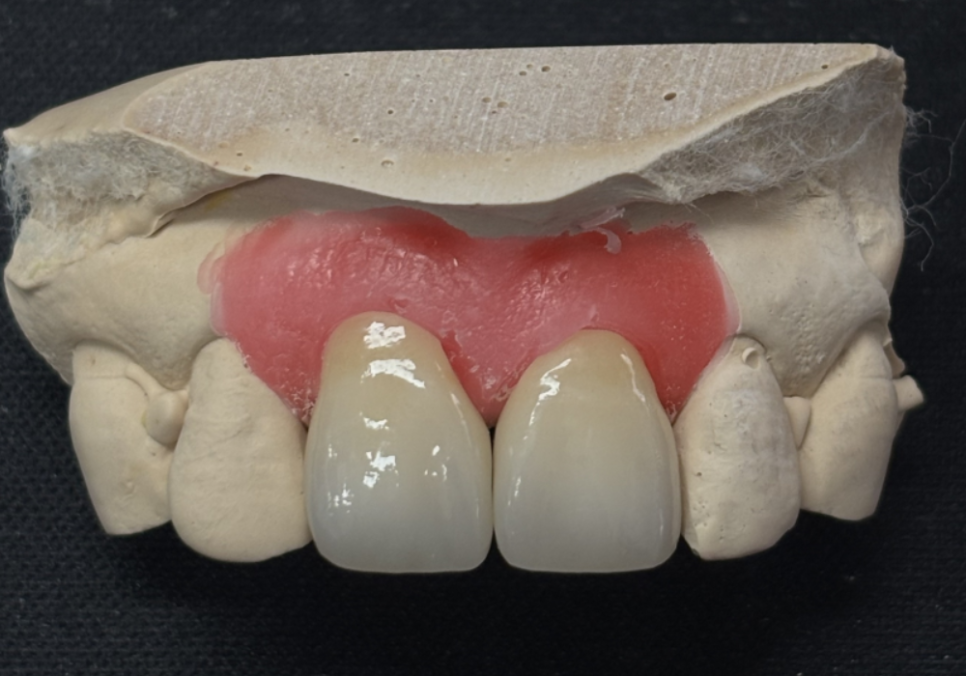

다행히 앞니(#11, 21)를

정밀하게 살펴본 결과

금이 치아 겉면에만

머물러 있는 상태였습니다.

신경이라는 예민한 통로까지는

손상되지 않아 신경치료 없이

크라운 치료로 진행하기로 했는데요.

이런 고민을 덜어드리기 위해

저희는 치과 안에 기공소를 직접 운영하고 있습니다.

보통 외부 업체에 맡기면

소통 과정에서 미세한 톤 차이가 생길 수 있지만

원내 기공소에서는

제가 기공사분과 실시간으로 소통하며

환자분 고유의 치아

색상과 투명도를 정밀하게 맞출 수 있죠.

심지어 환자분이 체어에 앉아 계신 상태에서

직접 색상을 대조하며 수정하는

세밀한 작업도 가능합니다.

251229 (전) 260114(후)

이번 환자분 역시 옆 치아와 이질감이

전혀 느껴지지 않도록

자연스러운 지르코니아로 완성해 드렸습니다.^^